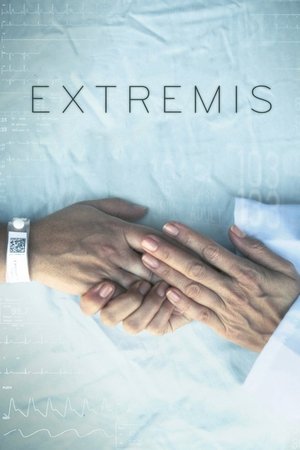

Extremis

6.954